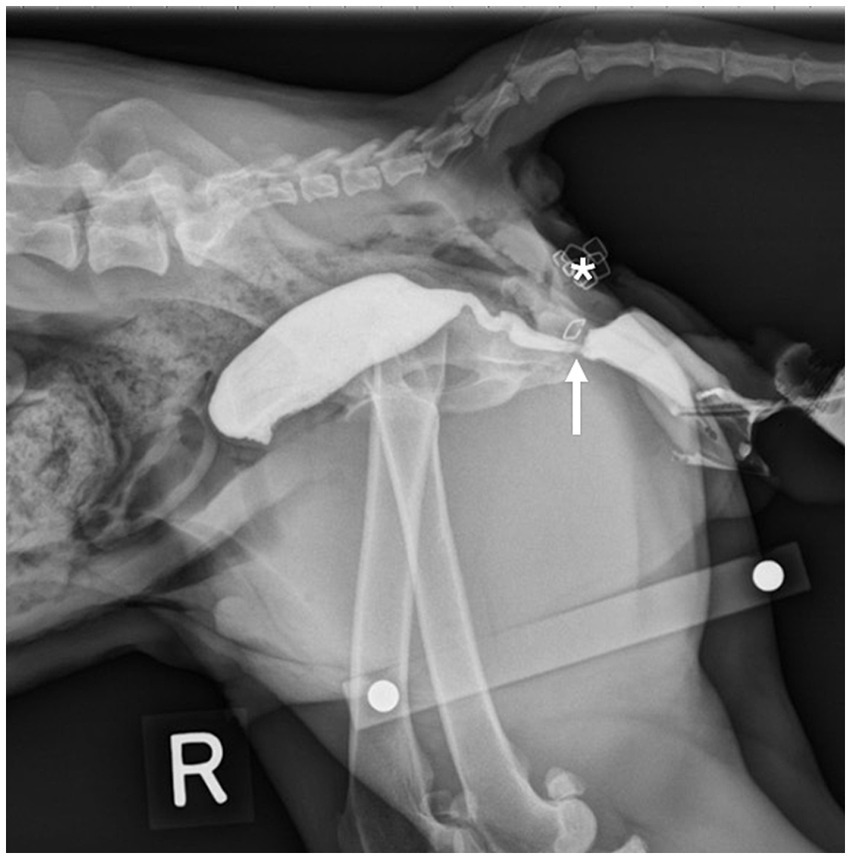

In Group B, positive contrast cystourethrography and positive contrast vaginography (Omnipaque, iohexol 240 mgI/mL) were performed to highlight the location of the vaginectomy and urethrostomy (Figure 5). Prior to injection of contrast media, the labia were sutured closed around the urinary catheter using 0 PDS in a simple continuous pattern to minimize contrast leakage. Following cystourethrogram, a vaginogram was performed after deflating the urinary catheter balloon and withdrawing the catheter into the vestibule while contrast was continually instilled. A right lateral radiograph was then taken.

Figure 5

www.frontiersin.org

Figure 5. Lateral radiograph of a Group B cadaver. A staple placed at the urethrostomy site can be seen to orient the viewer to the location of the caudal vestibular urethrostomy (arrow). Location of the transverse skin incision (*).